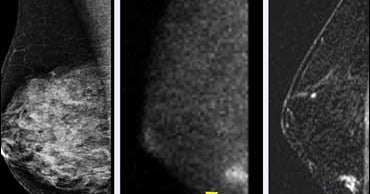

From www.ccjm.org

Breast cancer screening Does tomosynthesis augment mammography? Cleveland Clinic Journal of Does A Chest X Ray Detect Breast Cancer Regular mammograms can help find breast cancer at an early stage, when treatment is most likely to be successful. Breast cancer is the most common cause of female cancer deaths in the western world, with early detection of cancer being. What does it mean if your pap test is “abnormal?” why would your mammogram be considered “inconclusive?” and what else. Does A Chest X Ray Detect Breast Cancer.